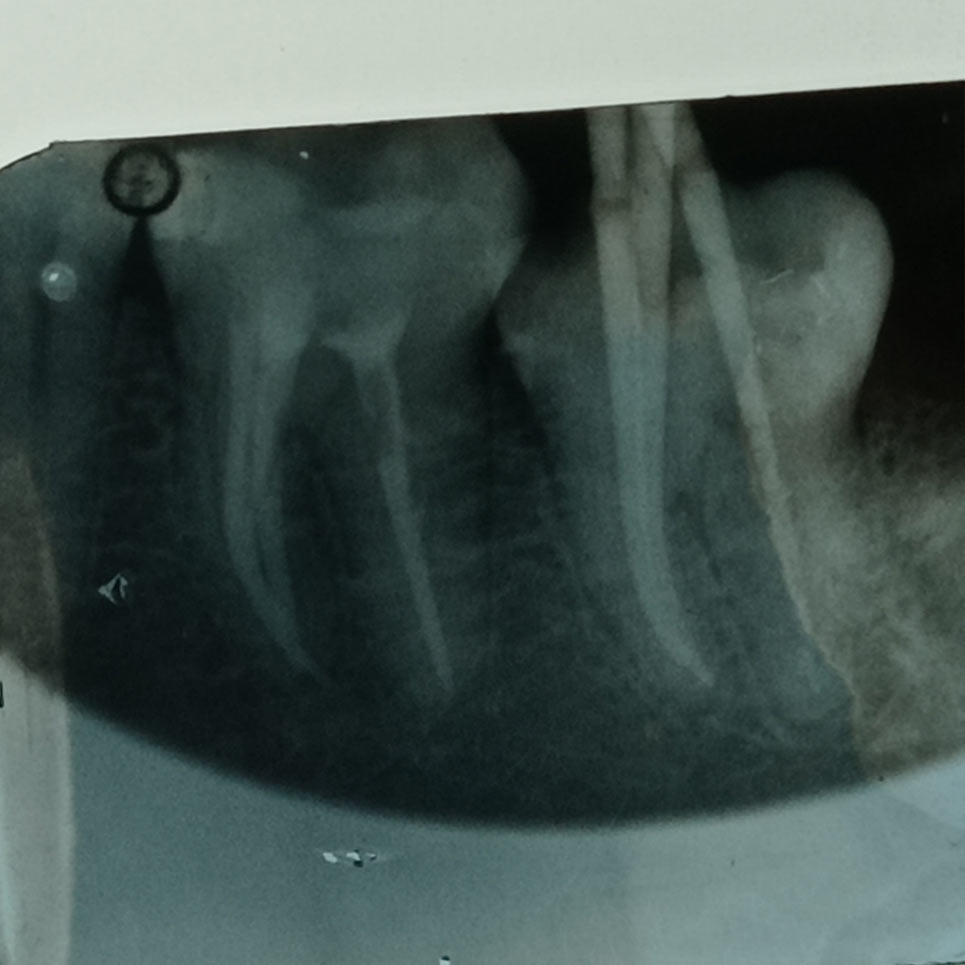

Η απονεύρωση, γίνεται όταν πλέον το δόντι έχει νεκρωθεί για κάποιο λόγο, βλέπε φλεγμονή, κάταγμα, εκτεταμένη τερηδόνα, είτε γιατί έχει σπάσει αρκετά και πρέπει στα πλαίσια της αναπλήρωσης του και αποκατάστασης να απονευρωθεί για να διατηρηθεί σωστά στο στόμα μας, είτε γιατί έχει κάποια κύστη.

Είμαστε εξειδικευμένοι ~ με ετήσια μετεκπαίδευση στον τομέα των απονευρώσεων ~ και πραγματοποιούμε τις θεραπείες μας, με όλα τα τελευταία μέσα και τεχνολογία, πλήρως εναρμονισμένοι, ενημερωμένοι, για το μέγιστο άρτιο αποτέλεσμα.